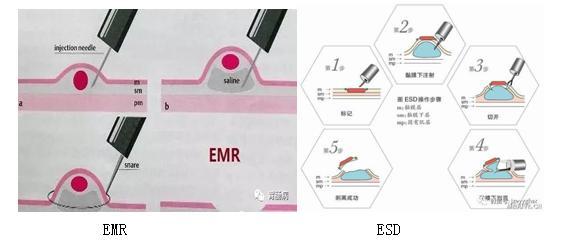

与外科手术相比,内镜下切除消化道良恶性肿瘤的技术具有创伤小、恢复快、并发症少等优势。其中,内镜下黏膜剥离术(ESD)、黏膜挖除术(ESE)为难度系数较大的手术方式,对面积较大、累积较深的病变能进行完整的切除,有效降低肿瘤残留及复发率。

内镜技术:ESD

内镜粘膜下剥离术(endoscopic submucosal dissection,ESD)是在内镜下黏膜切除术(EMR)基础上发展而来的新技术,内镜下使用高频电刀与专用器械,将胃肠道>2cm的病灶(包括胃肠道早期肿瘤)与其下方正常的粘膜下层逐步剥离,以达到将病灶完整切除的技术。

近年来,随着内镜诊疗技术及器械的不断进步,内镜粘膜下剥离术(ESD)治疗消化道良性肿瘤及消化道早期癌症病变往往可取得与外科手术相似的治疗结果,且具有微创、不改变消化道结构、避免外科手术风险及减少术后生活质量下降等优点,是一种经济、安全、可靠的治疗消化道浅表性病变的方法。ESD治疗的优势在于不需要外科手术就能完整切除肿瘤组织。